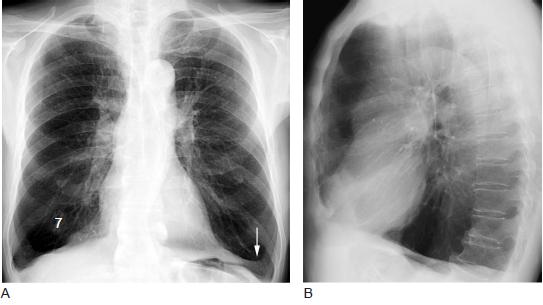

肺气肿的症状与病情轻重密切相关。早期可无症状或仅在劳动、运动时感到气短。随着肺气肿进展,呼吸困难程度随之加重,以至稍一活动甚或完全休息时仍感气短。患者感到乏力、体重下降、食欲减退、上腹胀满。伴有咳嗽、咳痰等症状,典型肺气肿者胸廓前后径增大,呈桶状胸,呼吸运动减弱,语音震颤减弱,叩诊过清音,心室浊音界缩小,肝浊音界下移,呼吸音减低,偶尔可听到干、湿啰音,心音低远。